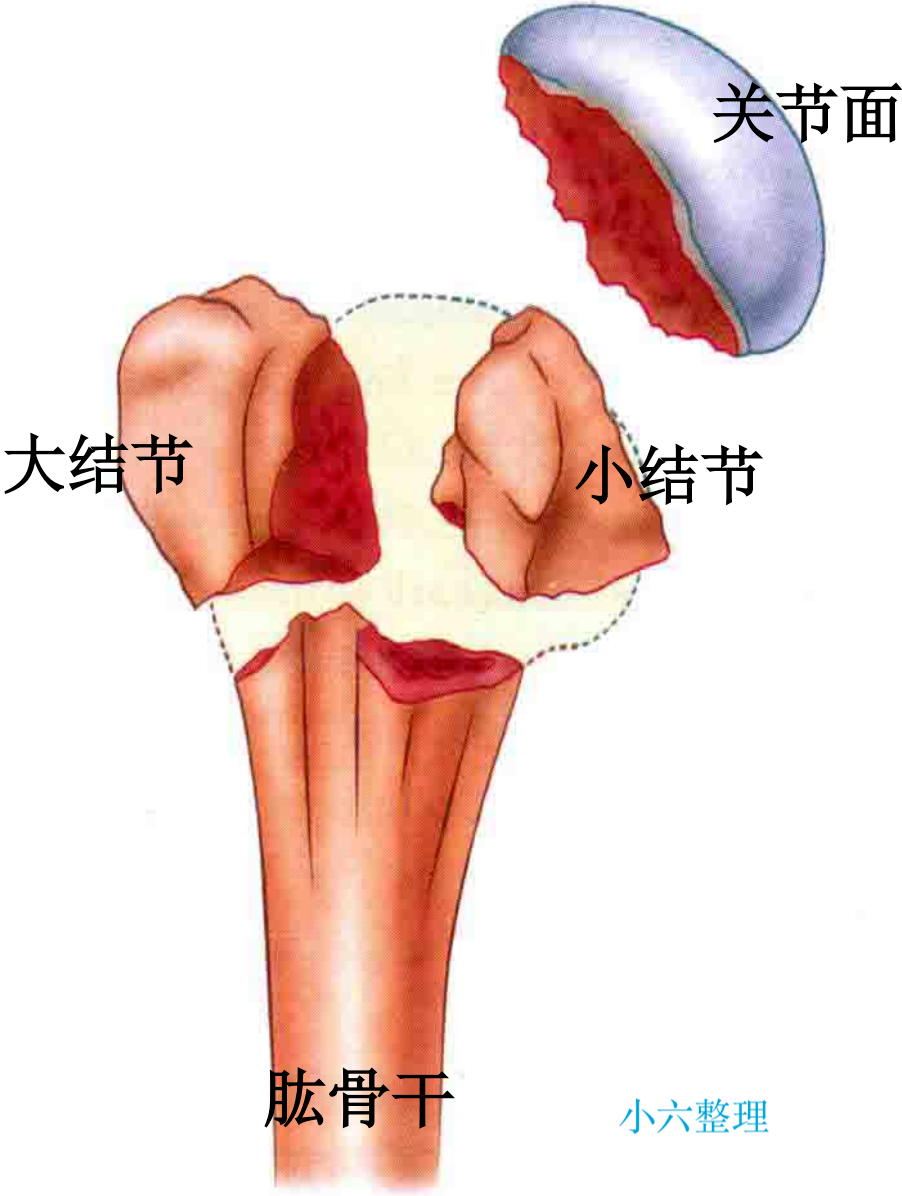

分型

第三部分是小结节和附着的肩胛下肌,具有内收和内旋的作用;

第四部分是肱骨干,从外科颈或结节下水平断裂。